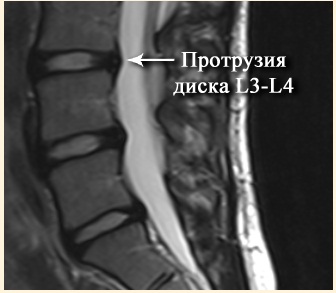

Грыжа позвоночника

Межпозвонковая грыжа вызывает у человека большое беспокойство. При грыже также можно использовать этот аппарат. Если болезнь зашла слишком далеко, следует обратиться к врачу.

В остальных случаях необходимо выполнить следующие действия:

- Прижмите устройство к пораженному позвонку.

- Зафиксируйте, держите 20-30 минут.

- Можно использовать второй вариант: расстелить одеяло, лечь на него спиной, полежать, пока боль не утихнет.

Можно ли применять аппликатор Кузнецова при грыже позвоночника

Как ни странно, не только можно, но и нужно. Ведь мы не стали утверждать, что этот простой физиотерапевтический прибор совершенно бесполезен или вреден. Если откинуть все фокусы магнитов, «биоэнергетической информационной системы», «резонансного поля» и «акупунктурных точек», то получается, что:

- аппликатор отвлекает пациента от болей в спине и улучшает качество жизни, позволяет снизить дозу лекарства;

- интенсивный кровоток позволяет значительно улучшить отток крови от мышц и глубоких связок спины.

При протрузиях и межпозвонковых грыжах важным патогенетическим фактором является воспаление, отек нервных корешков, мышц и связок. Понятно, что улучшение кровотока в конечном итоге улучшает венозный отток от очага воспаления.

А это снижает выраженность болевого синдрома и миофасциального синдрома, от которого зависит хронизация болей в спине;